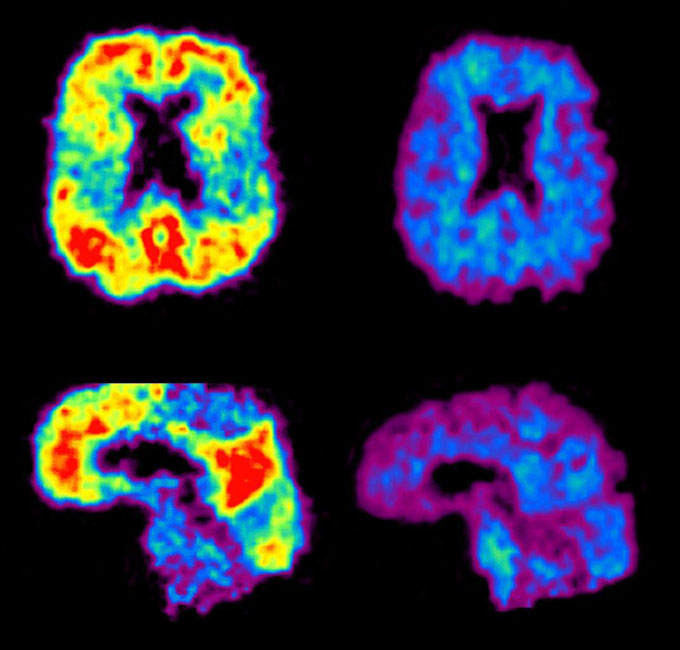

Decades ago, the only definitive way to get a diagnosis was an autopsy. Since then, scientists have figured out how to see the disease in living people. Spinal taps reveal levels of key proteins associated with the disease. And brain scans can illuminate the characteristic plaques and tangles that mar the brain in a person with Alzheimer’s disease.

But blood tests are not necessarily thoroughly tested for accuracy. In a head-to-head comparison of six commercially available tests, the tests that used p-tau217 accurately identified signs of Alzheimer’s disease, specifically amyloid accumulation in a PET scan, Schindler and her colleagues found. That work was described in a preprint on medRxiv.org and presented July 30 at the AAIC meeting.